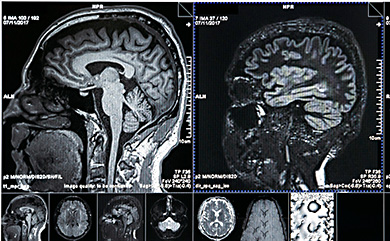

МРТ и МРА – магнитно-резонансная томография и магнитно-резонансная ангиография– безопасный метод исследования с помощью ядерного магнитного резонанса. Используется при поражениях головного и спинного мозга, заболеваний мягких тканей и костей, опухолей головы и шеи.